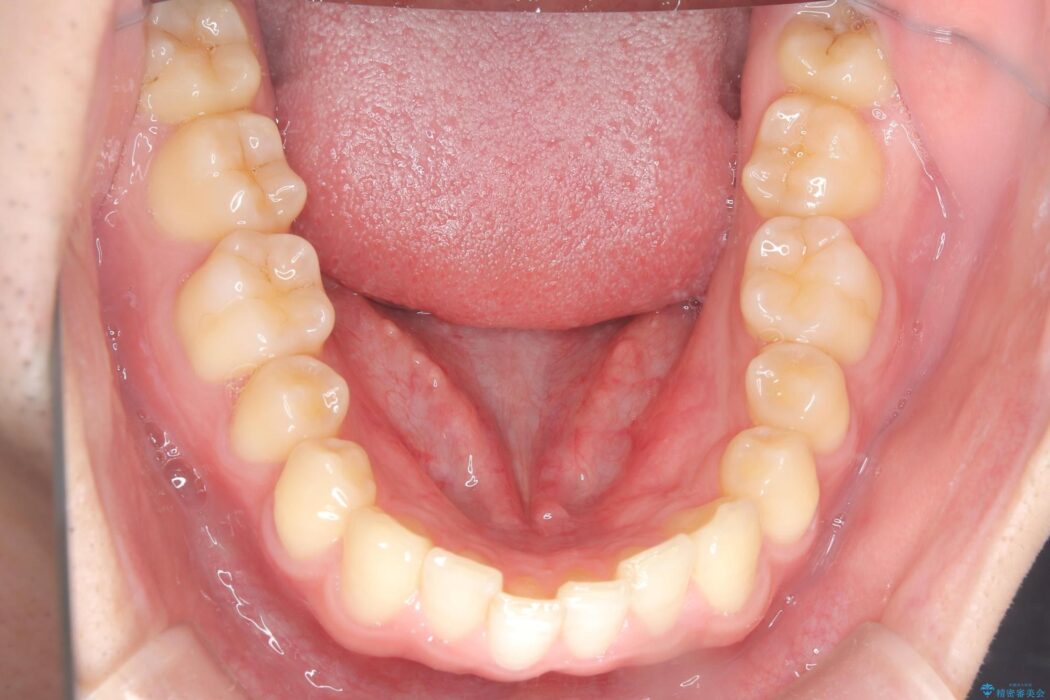

下顎の舌側傾斜気味の前歯も唇側へ歯軸傾斜させています。